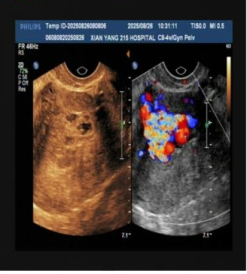

几天前,来自乾县的蒙女士被紧急送至陕西省核工业二一五医院妇科急诊。当时的她,面色苍白如纸,冷汗已浸湿衣衫,每一次呼吸都显得急促而费力。这一切,都源于蒙女士一个月前接受的药物流产加清宫手术,术后复查时发现宫腔内仍有组织残留。当地医院为她进行了为期10天的药物保守治疗。然而,就在停药后不久,她突然出现剧烈腹痛并伴有大量阴道出血,情况急转直下。B超提示宫腔内残留组织伴有异常丰富的血流信号,血HCG指标也高达490mIU/ml,情况危急,建议立即转入上级医院救治。

检查结果很快传来,B超结果显示宫腔内残留组织伴丰富血流,高度怀疑“子宫动静脉瘘”;随后的MRI检查进一步证实,患者宫腔内不仅有异常病灶,邻近子宫前壁还出现多发流空信号——这意味着子宫动脉与静脉之间形成了异常通道,动脉血直接涌入静脉,一旦通道破裂,就可能引发难以控制的致命性大出血。